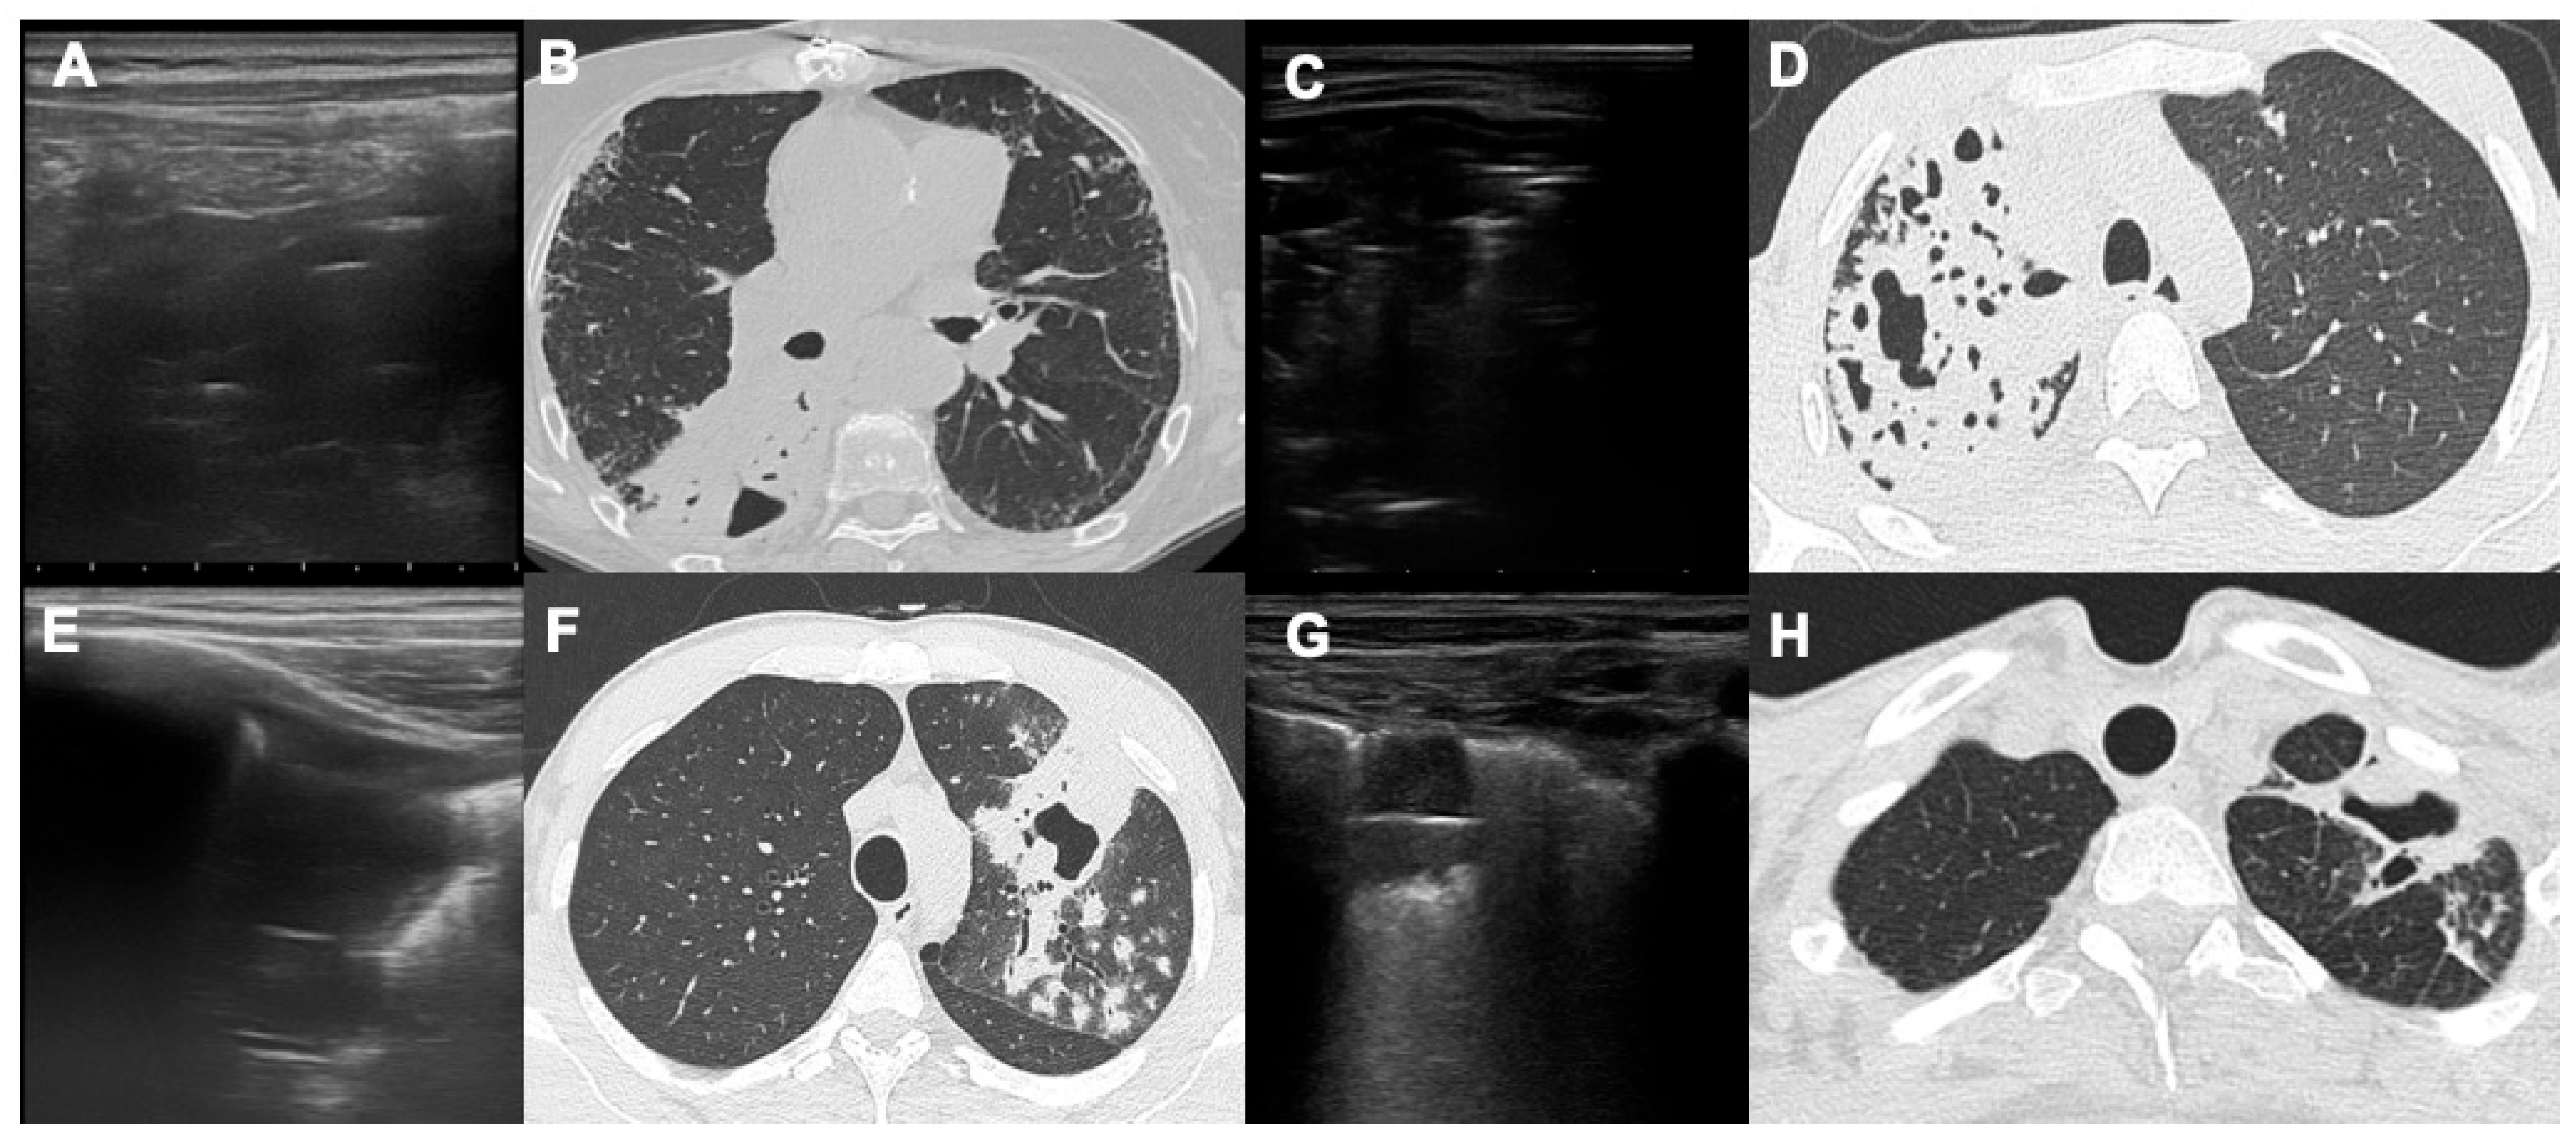

- Giannelli, F.; Cozzi, D.; Cavigli, E.; Campolmi, I.; Rinaldi, F.; Giachè, S.; Rogasi, P.G.; Miele, V.; Bartolucci, M. Lung ultrasound (LUS) in pulmonary tuberculosis: Correlation with chest CT and X-ray findings. J. Ultrasound 2022, 25, 625–634. [Google Scholar] [CrossRef]